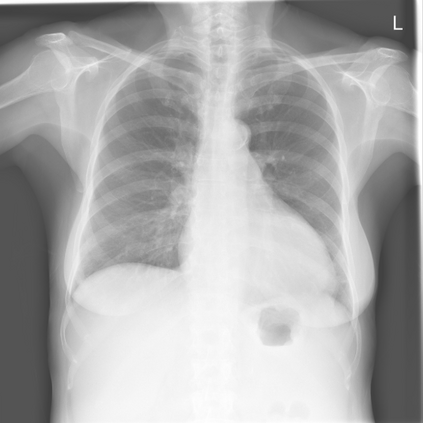

The remarkable success of deep learning has prompted interest in its application to medical imaging diagnosis. Even though state-of-the-art deep learning models have achieved human-level accuracy on the classification of different types of medical data, these models are hardly adopted in clinical workflows, mainly due to their lack of interpretability. The black-box-ness of deep learning models has raised the need for devising strategies to explain the decision process of these models, leading to the creation of the topic of eXplainable Artificial Intelligence (XAI). In this context, we provide a thorough survey of XAI applied to medical imaging diagnosis, including visual, textual, example-based and concept-based explanation methods. Moreover, this work reviews the existing medical imaging datasets and the existing metrics for evaluating the quality of the explanations. In addition, we include a performance comparison among a set of report generation-based methods. Finally, the major challenges in applying XAI to medical imaging and the future research directions on the topic are also discussed.